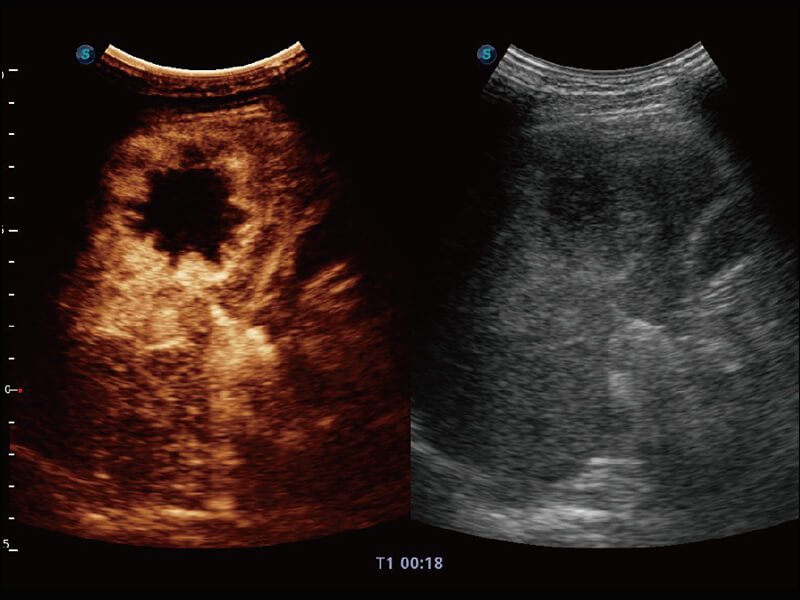

性能优异的硬件架构,极大提升超声系统的运行效率和数据处理能力。相比以往超声成像系统,Wis+平台为您带来极快的响应速度和成像帧频,提升检查流畅度。

S60探头工艺,从前端信号处理每一个环节采集无损声学数据,真实还原组织原貌,再现解剖细节。

超宽频带技术,为容积成像带来优质的二维图像基础,为您呈现丰富的结构细节,栩栩如生地展示宝宝的宫内形态以及各种组织的立体结构。